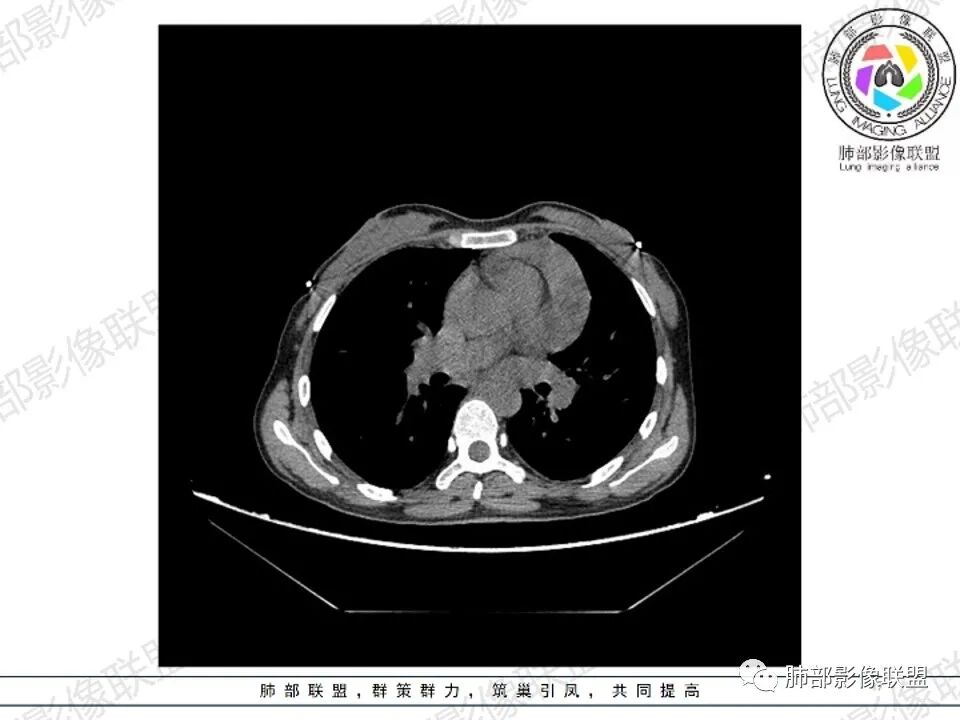

2.影像显示前纵隔不规则块状影,依势贴附心脏大血管旁,密度不均,边界不甚清楚,有结节融合感。

3.病灶轻度不均匀强化,可见血管穿行,散在液性低密度区。

双肺门未见肿大淋巴结。

4.双侧腋窝区见增大淋巴结,边界清楚。

1.年轻女性,前纵隔不规则块状影,密度不均,边界不甚清楚,有结节融合感,轻度不均匀强化,可见血管穿行,最常见最符合的无疑是淋巴瘤!